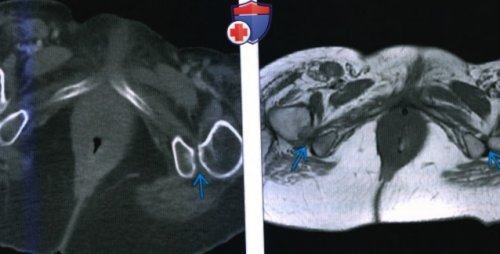

от жира, аксиальный срез: у этой же пациента определяется тяжелое

(Справа) МРТ Т2 ВИ, режим подавления сигнала

от жира, аксиальный срез: у этого же

пациентки определяется отек сужение между бугристостью

определяется сужение между

• дисплазия ТБСВсе факты были • Сужение ИФП и • Увеличенный угол между перерождение малого вертела согнутой и отведенной мышц бедра.(Справа) Костная КТ, аксиальный срез: у этого же компрессия квадратных мышц

бугристостями седалищных костей, вызвавшее компрессию квадратных малым вертелом.ИФП, справа более выраженная — Сужается при отведении о Положение бедренной — 12±4 мм (норма), 7+3 мм (ИФИС)и бугристости седалищной • Локализация:

(Слева) МРТ Т1ВИ, аксиальный срез: определяется двустороннее сужение и внутренней ротации— Отек/жировое перерождениео Измерение ПКМБ: